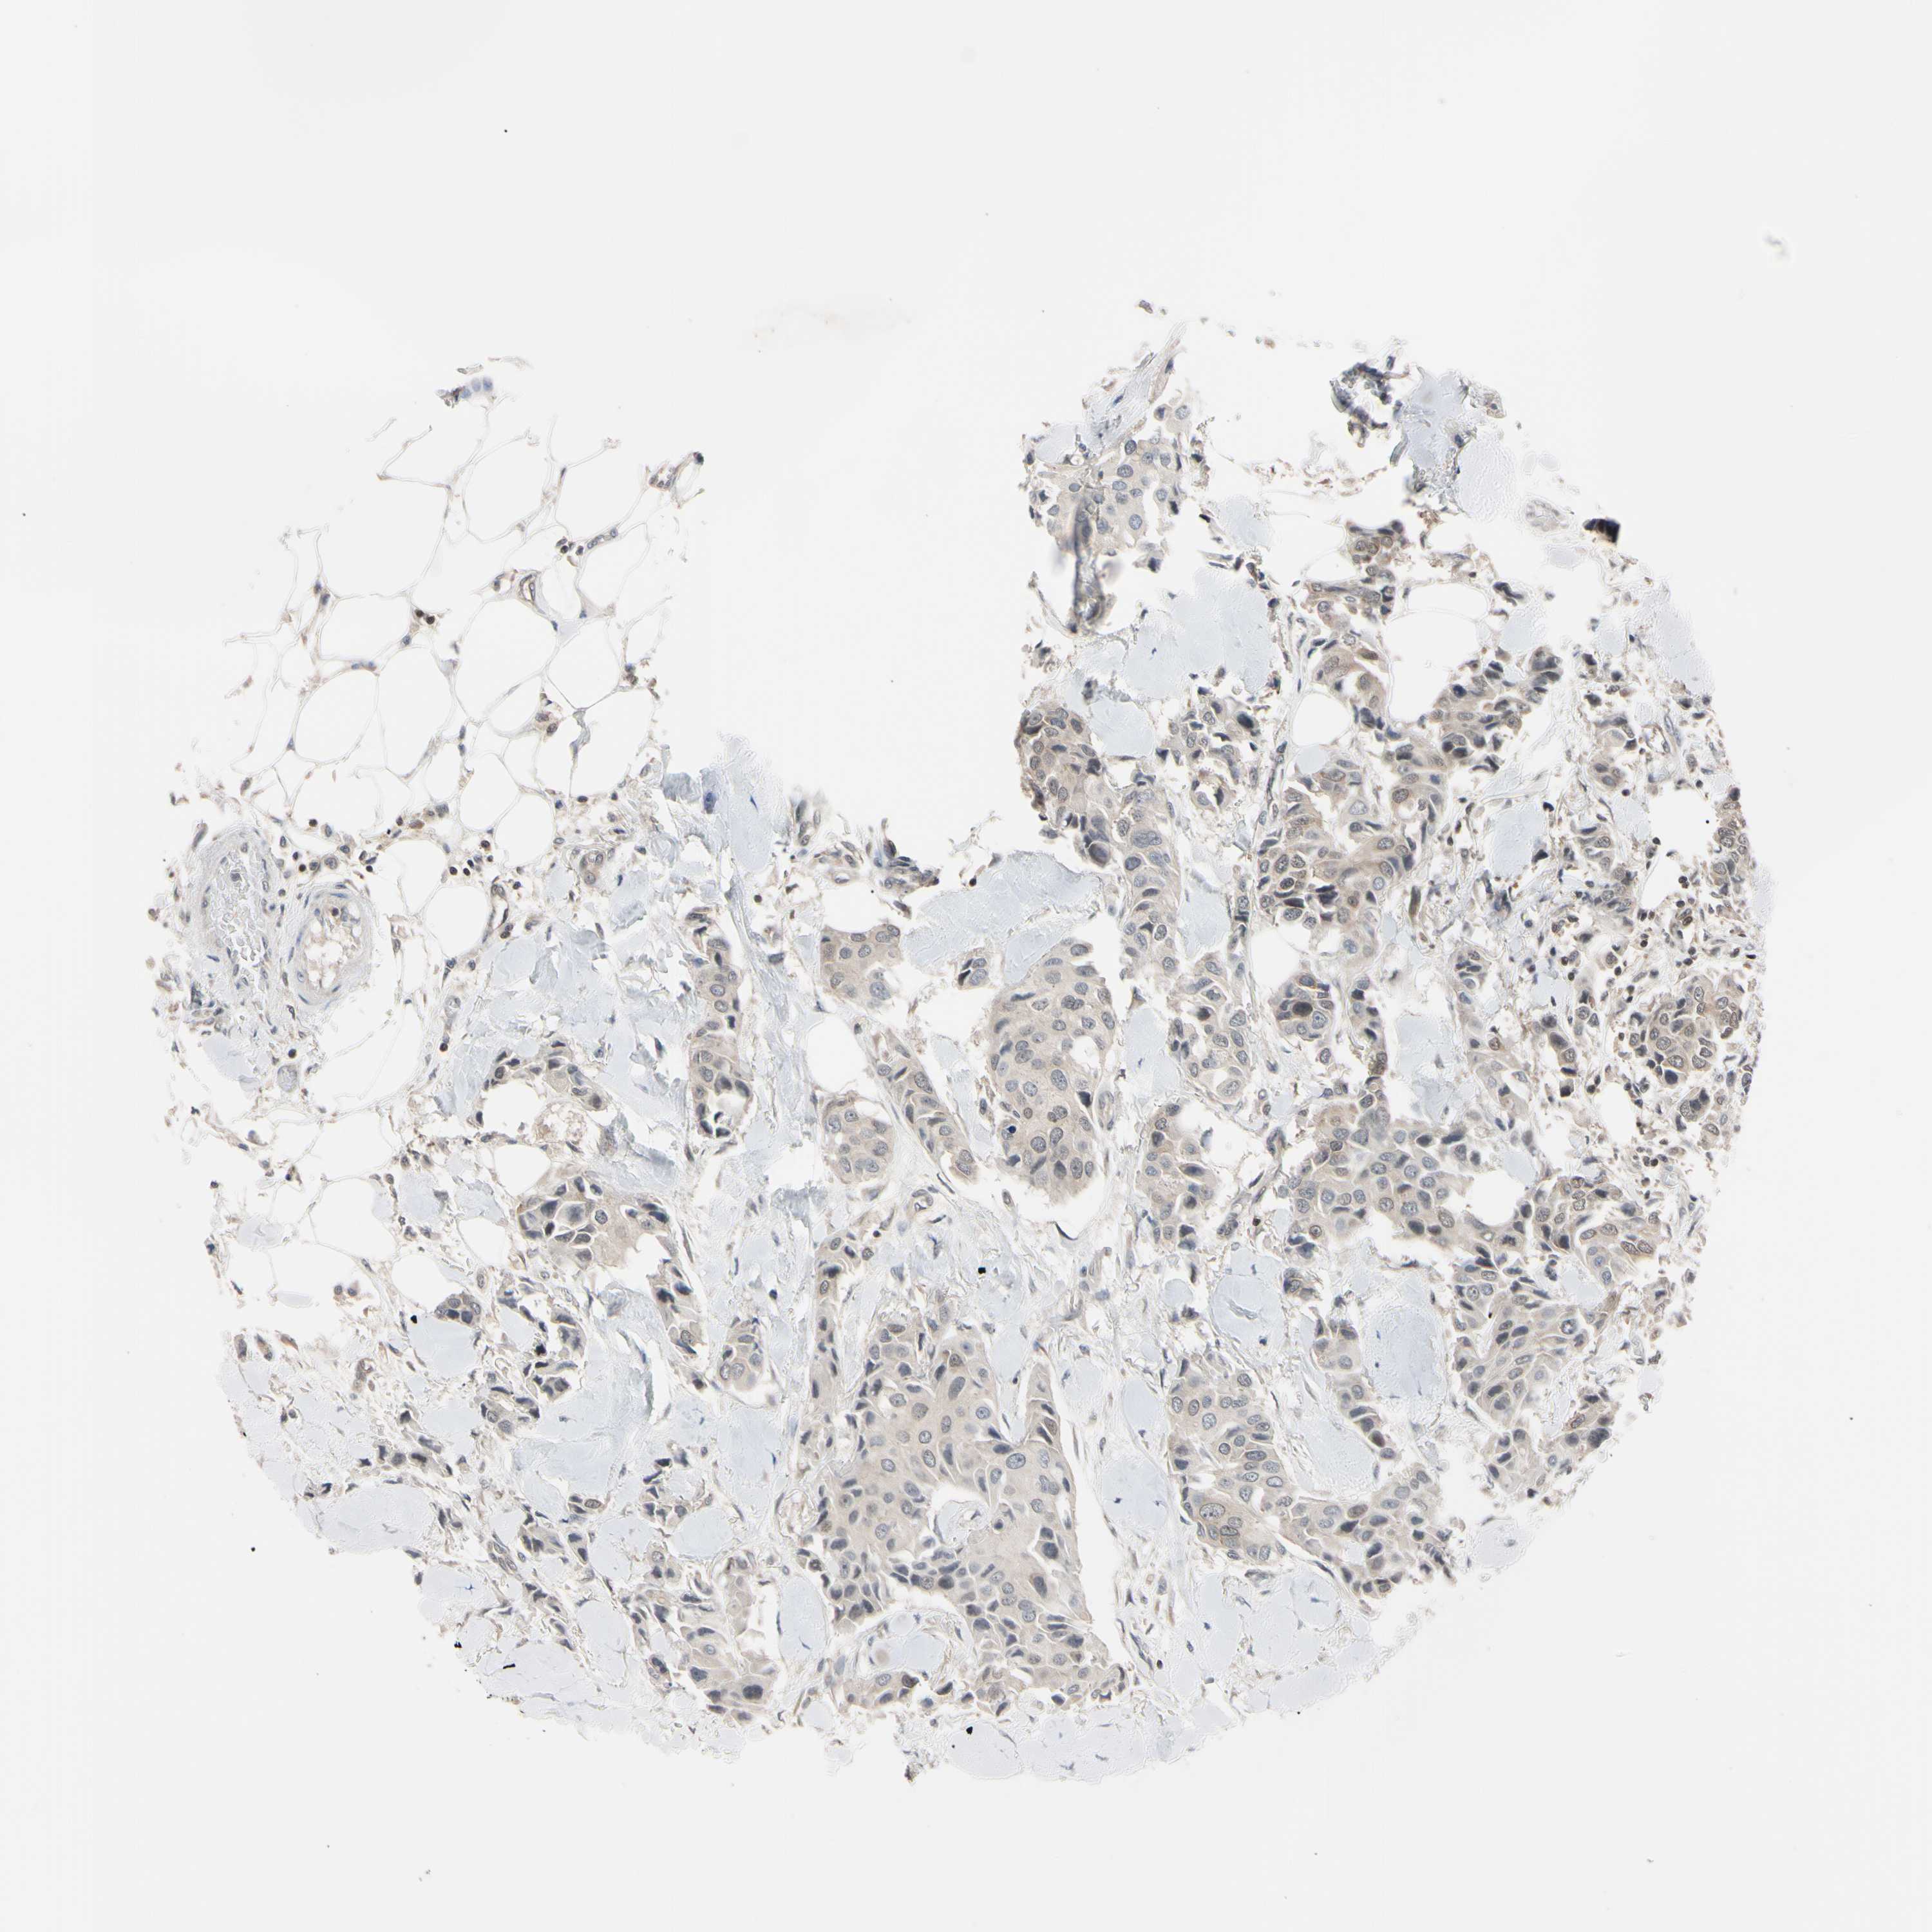

CANCER BREAST CANCER Show tissue menu

Breast cancer

Human cancer